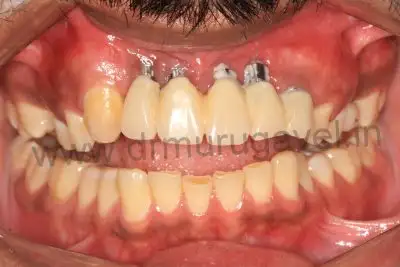

Before treatment image

Front teeth replacement with Implants

- It should be noted that his provisional bridge had hygienic gaps in the gum region , this denotes perfect gum healing and the implants condition was confirmed after taking radiographs ( OPG & CBCT ).

- The patient was happy with esthetics and teeth shape and size of his old provisional bridge , so the same replica of this was planned to do in permanent teeth also. The permanent bridge CAD CAM zirconia was delivered in 3 days .